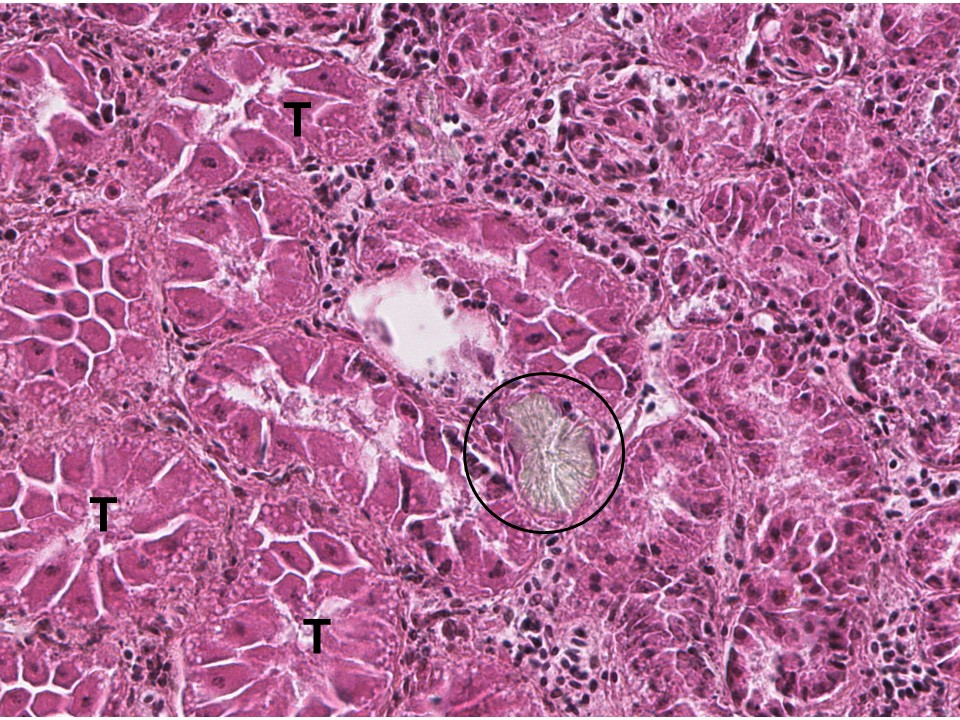

草酸鈣在H&E下的長相

A calcium oxalate crystal is seen in a renal tubule of a sandhill crane (Grus canadensis). These crystals, which have a broken glass appearance, are frequently associated with inflammatory cells. T: Normal renal tubules.

- 結晶的顯微特徵

- 在偏光顯微鏡下,草酸鈣呈 強雙折射、形態多為放射狀花束或菊花狀(rosettes/sheaves)。